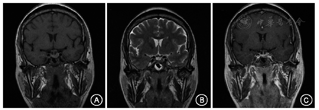

体格检查:轻度肢端肥大症面容,表现为口唇略肥厚(图1);手足宽大,手指/足趾节增粗,下肢皮肤增厚。辅助检查:(2017年7月)血总皮质醇268.66 nmol/L(参考值:110.56~616.37 nmol/L),促肾上腺皮质激素(ACTH)3.44 pmol/L(参考值:0~10.13 pmol/L),催乳素0.56 nmol/L(参考值:<1.30 nmol/L),胰岛素样生长因子1(IGF-1)276 μg/L(参考值:81~225 μg/L),清晨随机血清生长激素(GH)1.3 μg/L(参考值:<2.0 μg/L),甲状腺功能正常。空腹血生化:血糖6.4 mmol/L(参考值:3.9~6.1 mmol/L),血钙2.35 mmol/L(参考值:2.13~2.70 mmol/L),血钠142 mmol/L(参考值:135~145 mmol/L),血钾3.0 mmol/L(参考值:3.5~5.5 mmol/L)。垂体增强MRI示垂体左翼后下部占位,大小约6.0 mm×3.5 mm,考虑为垂体微腺瘤(图2)。口服75 g葡萄糖GH抑制试验:GH基础值为2.1 μg/L,谷值为0.7 μg/L。

注:A. T1WI;B. T2WI;C.增强MRI;垂体左翼上缘膨隆,下缘倾斜,垂体平扫信号均匀,呈等T1等T2信号;增强MRI显示垂体偏左翼后下部一不规则强化减低区;视交叉未见受压上移征象,双侧海绵窦未见明显异常